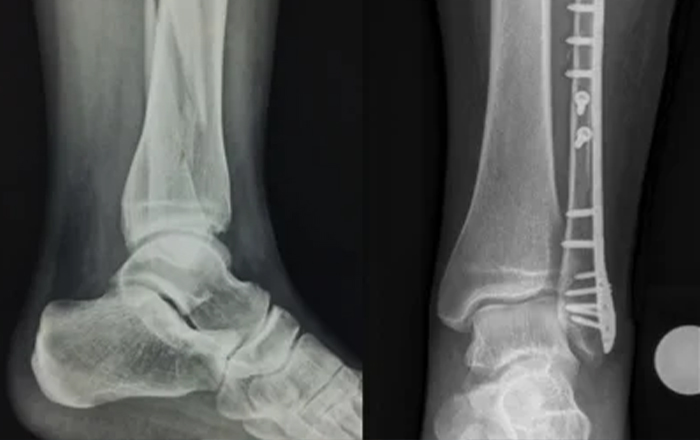

• İç ve dış fiksasyon sistemleri